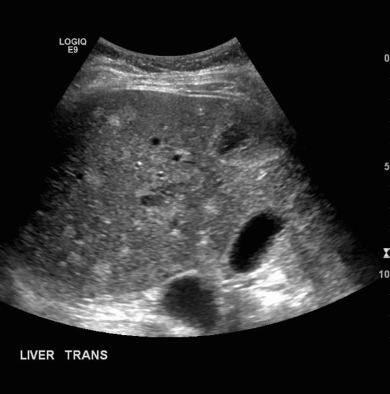

US finding

- 다양한 크기로 다발성

- 다수 발생 시 간종대 발생

- 60~70% 다낭성 신질환과 동반된다

- 낭종벽에 석회화 동반

- 격막이 형성되어 있다

polycystic liver disease ③ bile duct hamartomas